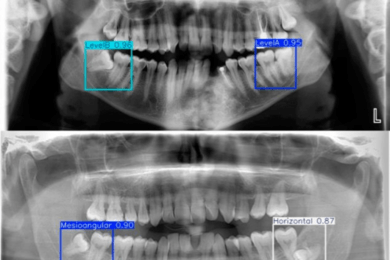

589

Автоматизация рентген-анализа для ортодонтов

#Фирменный стиль

#Разработка программного обеспечения